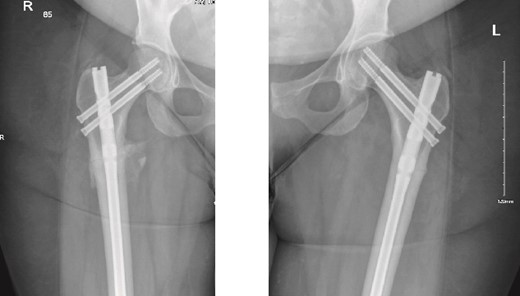

The patient was seen in the clinic at 2 weeks, 6 weeks, and 6 months post-surgery. She was doing well, reporting only mild pain. She was fully weight-bearing with the assistance of a cane and had good range of motion (Figs 3 and 4).

6-months follow-up anteroposterior (AP) view of the right and left femurs after CRIF with IM nail.

As part of the follow-up, the endocrinology team continued to monitor the patient for further investigation into the possible causes of the fractures. A BMD scan was performed and showed normal results. Based on their assessment, the endocrinology team diagnosed the patient with osteomalacia, most likely of nutritional origin.